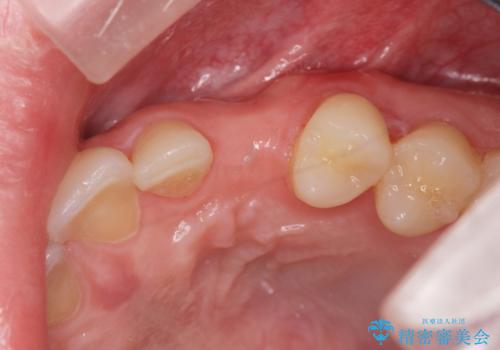

- 目立つ前歯の欠損の状況を改善されたい、と希望され来院されました。

歯を削らず、インプラント治療でもない方法を希望されたのでバネの目立たないノンクラスプデンチャーを製作します。